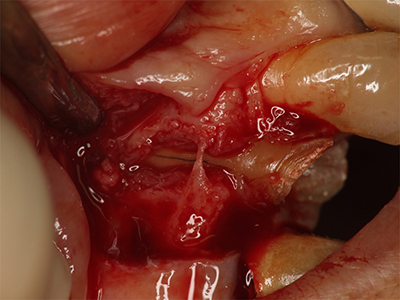

歯根のクラック(ひび割れ)の例

歯根が破折したりひび割れを起こすと、根管治療では治らず、しばしば抜歯の適応になる。歯の神経が無くなると、破折やひび割れを起こしやすくなってしまう。

根管治療に伴う最大のリスクは、歯根破折やクラック(ひび割れ)です。

根管治療を行った歯には歯髄(しずい;神経)がありません。歯髄には毛細血管が豊富に含まれ、これが歯に栄養供給を行っています。歯髄が無くなった歯は栄養供給がないため、枯れ木のように脆い状態になってしまいます。

一日平均して600回以上も咀嚼するため、根管治療をした歯は、特に硬いものを食べなくても破折したりひび割れたりすることがあります。これは不可抗力ですので、予防することは出来ません。

ひび割れによる抜歯

歯根のクラック(ひび割れ)によって抜歯となった歯。歯は、歯髄が無くなると脆くなり、しばしば破折やひび割れを起こす。